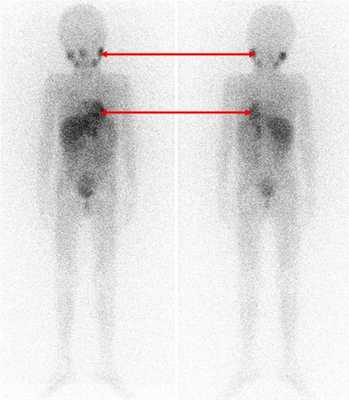

Радиоизотопные исследования

Одним из наиболее информативных специфических методов топической диагностики нейробластом является сцинтиграфия с метайодбензилгуанидином (МЙБГ), меченным 123I. МЙБГ по своей химической структуре сходен с катехоламинами в организме. Это вещество концентрируется в тех опухолях, которые вырабатывают катехоламины. МЙБГ метят радиоактивным изотопом йода (например, 123I) в безопасной для жизни дозе, и готовый препарат внутривенно вводят в кровоток. Накапливаясь в клетках опухоли, он дает излучение. Эти сигналы регистрирует специальная камера и переводит их в изображение. Таким образом, метод позволяет выявить не только первичную опухоль, но и наличие регионарных и отдаленных метастазов (рис. 7).

Рис. 7. Сцинтиграфия с метайодбензилгуанидином (визуализируется первичная паравертебральная опухоль с метастазами в кости черепа)